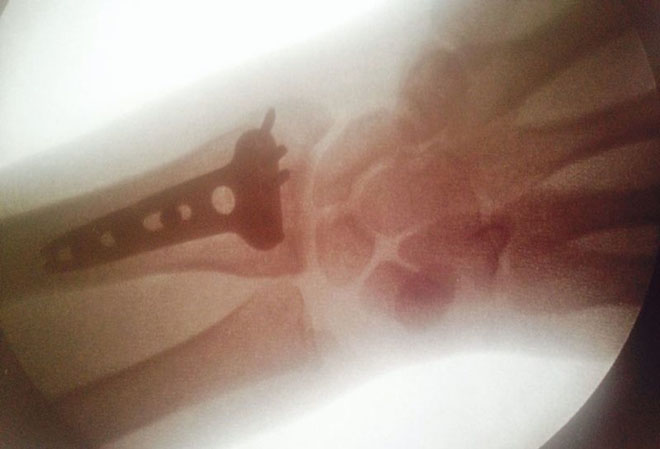

Tommy wurde am Montagmorgen in einem thailändischen Krankenhaus operiert, wobei der Bruch der Speiche am linken Handgelenk mit einer Metalplatte fixiert wurde. Gestern bekam der 24-jährige Engländer dann die Freigabe nach Hause zu fliegen, wo er sich weiteren Untersuchungen durch einenSpezialisten unterziehen wird. Dieser geht aber nach der Sichtung der ihm im Vorfeld zugemailten Röntgenbilder von einer kompetent durchgeführten und erfolgreich verlaufenen Operation aus.